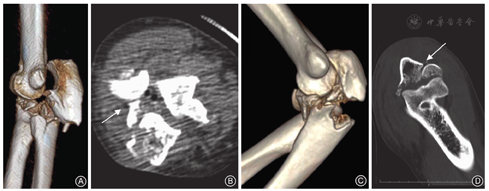

孟氏骨折(Monteggia fracture)指尺骨骨折伴上尺桡关节脱位,临床少见。其本质为尺骨骨折成角后,上尺桡关系破坏,导致桡骨头脱位。1814年,由Giovanni Battista Monteggia首次描述[1]。1967年,Bado[2]根据骨折脱位方向将孟氏骨折又分为4型:Ⅰ型,尺骨干骨折向前成角,桡骨头向前脱位;Ⅱ型,尺骨干骨折向后成角,桡骨头向后或后外侧脱位;Ⅲ型,尺骨干骺端骨折伴桡骨头向外及前外侧脱位;Ⅳ型,尺桡骨近端1/3双骨折合并桡骨头前脱位。Jupiter等[3]研究发现,后向的孟氏骨折脱位更加复杂、多变,因此他将尺骨近端骨折合并桡骨头后脱位(肱桡关节后脱位)(图1A,图1B)称为后孟氏骨折。目前在临床中,尺骨近端骨折合并桡骨头后脱位(肱桡关节后脱位)的损伤,伴或不伴有上尺桡关节脱位,均被称为后孟氏骨折。而经典孟氏骨折的严格定义是尺骨骨折伴上尺桡关节脱位。因此,对于不伴有上尺桡关节脱位的尺骨骨折(图1C,图1D),可称为经尺骨近端骨折后脱位。

后孟氏骨折与经尺骨近端骨折后脱位不同点:①后孟氏骨折存在上尺桡关节脱位,包括上尺桡关节单纯脱位(尺骨桡切迹完整,无移位骨折,桡骨头自上尺桡关节内脱出,伴有环状韧带破裂,近端骨间膜损伤,图2A)及尺骨桡切迹破裂脱位(桡骨头自尺骨桡切迹脱出时,尺骨桡切迹粉碎骨块与桡骨共同移位,骨块嵌插于上尺桡间隙内,同时合并环状韧带破裂,近端骨间膜损伤,图2B);而经尺骨近端骨折后脱位上尺桡关节完整,包括无脱位(尺骨冠突骨折一般为前方骨折,骨折未累及尺骨桡切迹,上尺桡关系紧密,环状韧带完整,骨间膜完整,图2C)及桡骨头伴有完整上尺桡切迹移位(尺骨桡切迹骨折块完整,骨折块大,环状韧带完整,近端骨间膜损伤,图2D);②后孟氏骨折冠突多为粉碎;而经尺骨近端骨折后脱位,骨块多为完整。